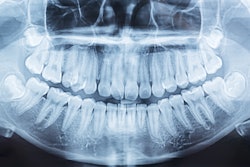

Since nearly 3 in 4 healthy kids may present with at least one dental abnormality or pathology, dentists should order panoramic x-rays at ages 9, 12, and 15 to detect them. The study was published on June 17 in the International Journal of Paediatric Dentistry.

The study validates the diagnostic efficacy of panoramic x-rays for diagnosing developmental dental anomalies and pathologies (DDAPs) in pediatric dental patients, the authors wrote.

To evaluate the age-based prevalence of DDAPs on panoramic x-rays and to determine when the appropriate age is to detect these conditions, the authors conducted an observational cohort study. X-rays from 581 patients between the ages of 6 and 19 were reviewed to identify anomalies of size, shape, position, structure, and other developmental anomalies and pathologies of the face and neck region, they wrote.

Of the children, 411 (74%) had at least one anomaly. Of the anomalies, 12% were shape-related; 17% were number-related; 28% were positional-related; and 63% were other dental anomalies and pathologies, including condylar erosion, vascular calcifications, and fibrous dysplasia, the authors wrote.

The optimal Youden index cutoff, which measures the effectiveness of a diagnostic marker and allows for the optimal cutoff point for the marker, for any anomaly was age 9, with an area under the curve (AUC) of 0.73 (95% confidence interval [CI], 0.68 to 0.77). After the first cutoff at age 9, the next was at age 12 (AUC: 0.65; 95% CI, 0.59 to 0.71), and age 15 was the optimal secondary cutoff for both number and positional anomalies (AUC: 0.57; 95% CI, 0.48 to 0.65; AUC: 0.64; 95%CI, 0.58 to 0.71, respectively), they wrote.

“(For early and timely detection), PRs should be prescribed at ages 9, 12, and 15 years for the diagnosis of DDAP (developmental dental anomalies and pathologies),” Schulman and colleagues concluded.